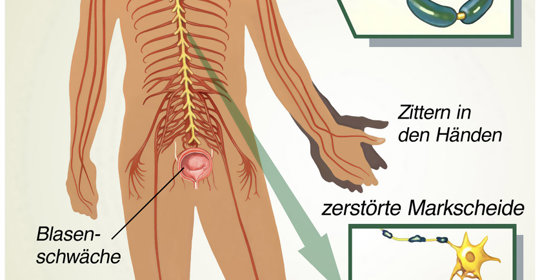

職業神經症:與精神疾病的區別在於症狀與來源的不同

職神:與憂鬱症的五個差別

肌陣攣:生活方式干預、藥物治療、神經調節